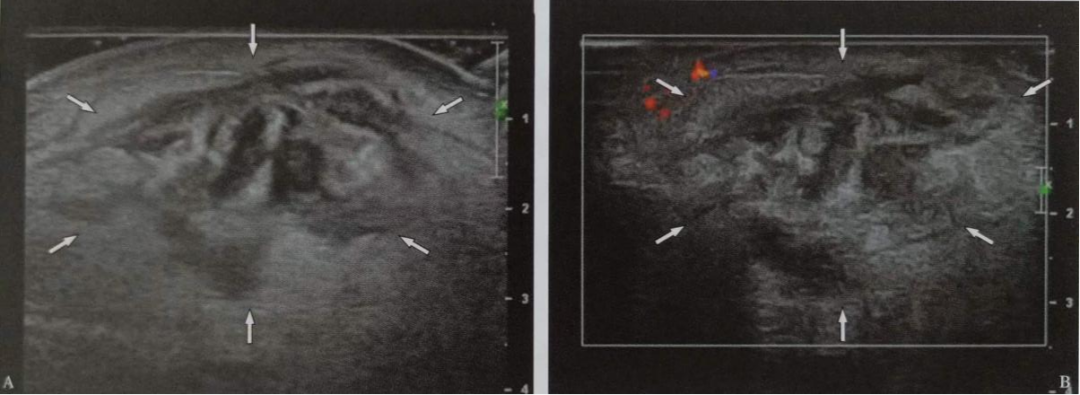

(3)皮膚腫瘤性疾病的良惡性鑒別。

如:鮑恩病、黑色素瘤、鱗狀細(xì)胞癌、脂溢性角化、日光性角化等。

圖片

黑色素瘤